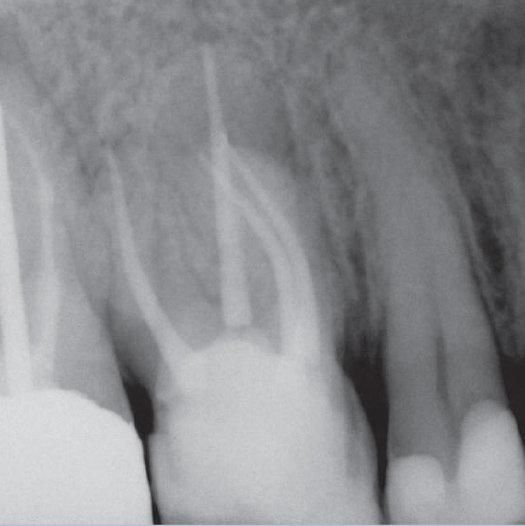

After

After Root Canal treatment